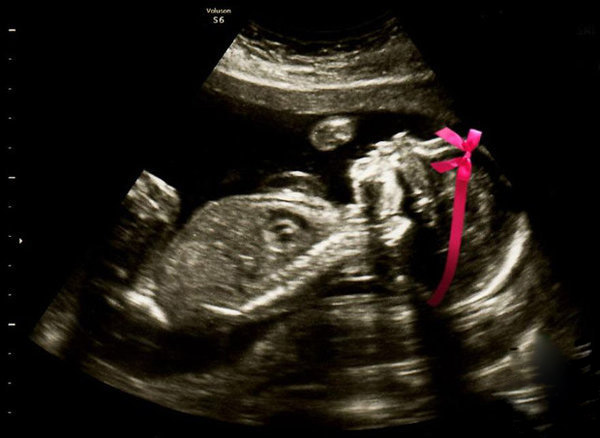

4- Cinsiyetini öğrendik!

Hamilelik haberini, Bebeklerinin cinsiyetinin ultrason fotoğrafıyla duyuran çift, aynı zamanda sosyal medyada sürdürülebilecek bir akıma da imza atmış.